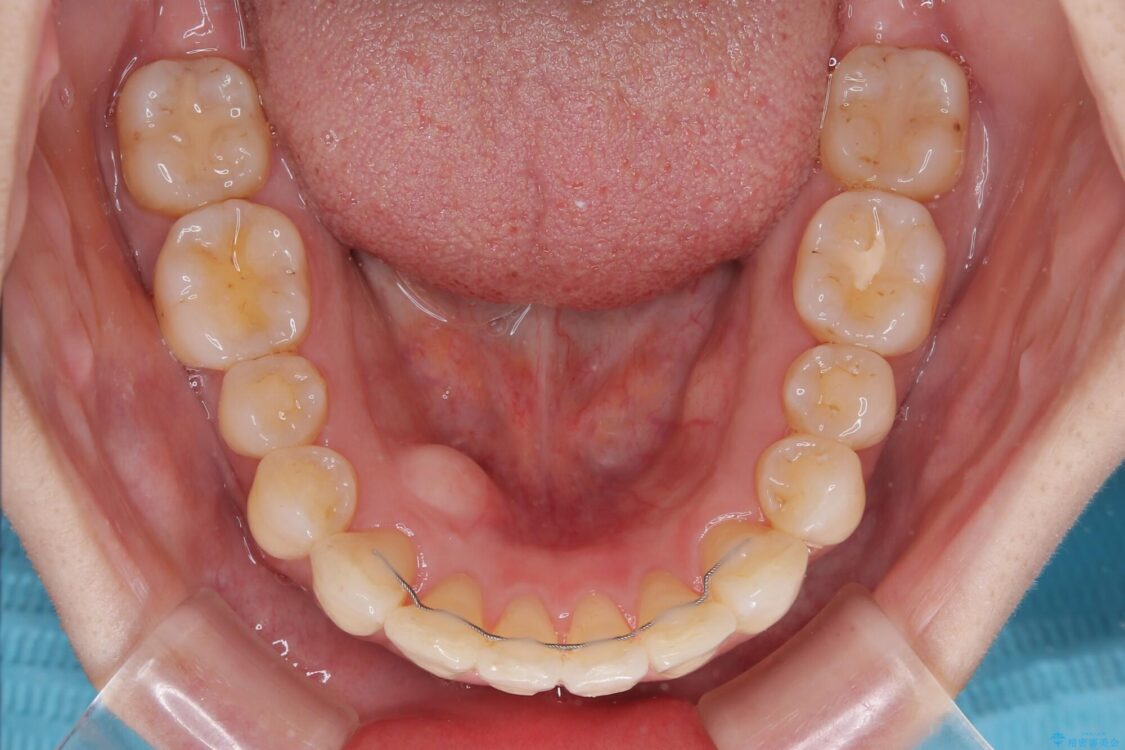

治療後

• インビザラインによる矯正治療と奥歯のインプラント治療 治療後画像